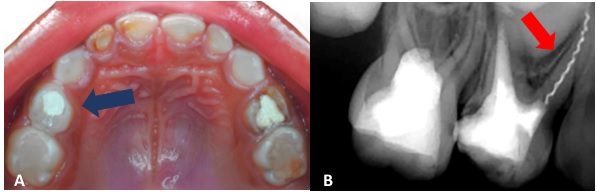

Una paciente pediátrica de sexo femenino, de 4 años y 11 meses de edad, acudió de urgencia a la Clínica de Odontopediatría de la Universidad Privada San Juan Bautista (Lima, Perú), acompañada de su madre. Esta refirió que su hija estaba recibiendo tratamiento del conducto cuando, al momento de finalizar el sellado, realizó un movimiento inesperado, lo que provocó la fractura del instrumento endodóntico. En el examen clínico odontológico, la niña mostró un comportamiento positivo, según la Escala de Frankl (16). El primer molar superior deciduo del lado derecho presentaba una restauración temporal (figura 1A) y dolor a la percusión vertical. Radiográficamente, en la pieza 54 se observó una imagen radiopaca (IRO) coronal compatible con una restauración. Además, se identificó una IRO intraconducto en la raíz distovestibular, sugestiva de material de obturación del conducto radicular; y, en la raíz mesiovestibular, se evidenció una IRO compatible con un léntulo fracturado de aproximadamente 7 mm de longitud, con aparente sobrepaso apical.

Asimismo, se observó un ensanchamiento del espacio del ligamento periodontal en la superficie distal de la raíz mesiovestibular. A nivel interradicular, se identificó una imagen radiolúcida (IRL) con pérdida de la lámina dura, junto con reabsorción radicular en el tercio apical de la pieza (figura 1B). El diagnóstico pulpar fue de tratamiento de conducto previo, mientras que el diagnóstico periapical correspondió a periodontitis apical sintomática del primer molar superior deciduo, con fractura de un instrumento en el conducto mesiovestibular. Se indicó la extracción del instrumento endodóntico fracturado, seguido de un retratamiento del conducto radicular.

Figura 1. Examen clínico y radiográfico de la pieza 54. A) Vista oclusal del maxilar superior, en la que se observa la pieza 54 con restauración temporal. B) Radiografía periapical de la pieza 54, donde se observa imagen radiopaca proyectada en raíz mesiovestibular compatible con fractura de instrumento endodóntico.